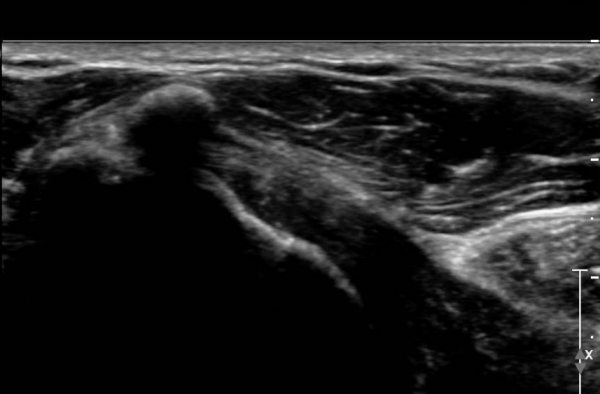

±Ø»ó°Ç Á¾´Ü¸é°Ë»ç»ó ±Ø»ó°Ç ¾Õ(»çÁø 4), Áß°£(»çÁø 5), ÈĹæ(»çÁø 7)¿¡ ±¤¹üÀ§ÇÏ°Ô ¼®È¸¸¦ º¸À̰í

Ⱦ´Ü¸é°Ë»ç(»çÁø 6)¿¡¼­µµ ±Ø»ó°Ç ³»ÃøºÎÅÍ ¿ÜÃø±îÁö ±¤¹üÀ§ÇÑ ¼®È¸°¡ °üÂûµÈ´Ù.

¿ªµ¿Àû°Ë»ç¿¡¼­ ¼®È¸°¡ °ßºÀ°ú Ãæµ¹ÇÏ´Â °ÍÀ» È®ÀÎÇÒ ¼ö ÀÖ´Ù(÷ºÎ µ¿¿µ»ó 1).